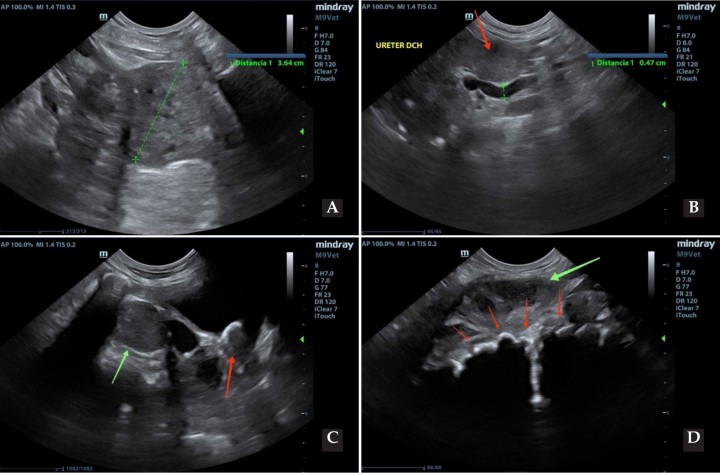

En vista de los hallazgos presentes, se recomendó la realización de una ecografía abdominal (Fig. 3).

<p>Imágenes ecográficas de prostatomegalia (línea verde) y alteración del parénquima (<strong>A</strong>), hidrouréter (línea verde) y adenopatía aórtica (flecha roja) (<strong>B</strong>), adenopatía iliaca (flecha verde) y urolito hiperecoico (flecha roja) en vejiga (<strong>C</strong>) y adenopatía iliaca medial (flecha verde) con sobrecrecimiento de los cuerpos vertebrales (flechas rojas) (<strong>D</strong>).</p>

Imágenes ecográficas de prostatomegalia (línea verde) y alteración del parénquima (A), hidrouréter (línea verde) y adenopatía aórtica (flecha roja) (B), adenopatía iliaca (flecha verde) y urolito hiperecoico (flecha roja) en vejiga (C) y adenopatía iliaca medial (flecha verde) con sobrecrecimiento de los cuerpos vertebrales (flechas rojas) (D).

Se visualizó la vejiga de la orina escasamente distendida con estructuras hiperecoicas productoras de sombras acústicas.

Se evidenció prostatomegalia, con parénquima heterogéneo y focos hiperecoicos, y uretra prostática hiperecogénica. Asimismo, los linfonodos ilíacos mediales aparecían redondeados e hipoecoicos, aumentados de tamaño y con reacción focal hiperecoica del retroperitoneo. Se tomaron muestras de próstata y linfonodos mediante aspiración con aguja fina (PAF) ecoguiada[ Ferré-Dolcet L: Abordaje clínico de las enfermedades prostáticas en el perro. Argos: Informativo Veterinario 2020; 219: 58-62. ] para su estudio citológico.

Además, se apreciaron irregularidades de las superficies óseas ventrales de los últimos cuerpos vertebrales y sacro, así como dilatación de la pelvis renal derecha y uréter derecho, el cual mantenía el mismo grado de dilatación hasta una lesión adyacente a la vejiga, de aspecto cavitada, sin poder evidenciar su entrada en el trígono vesical.